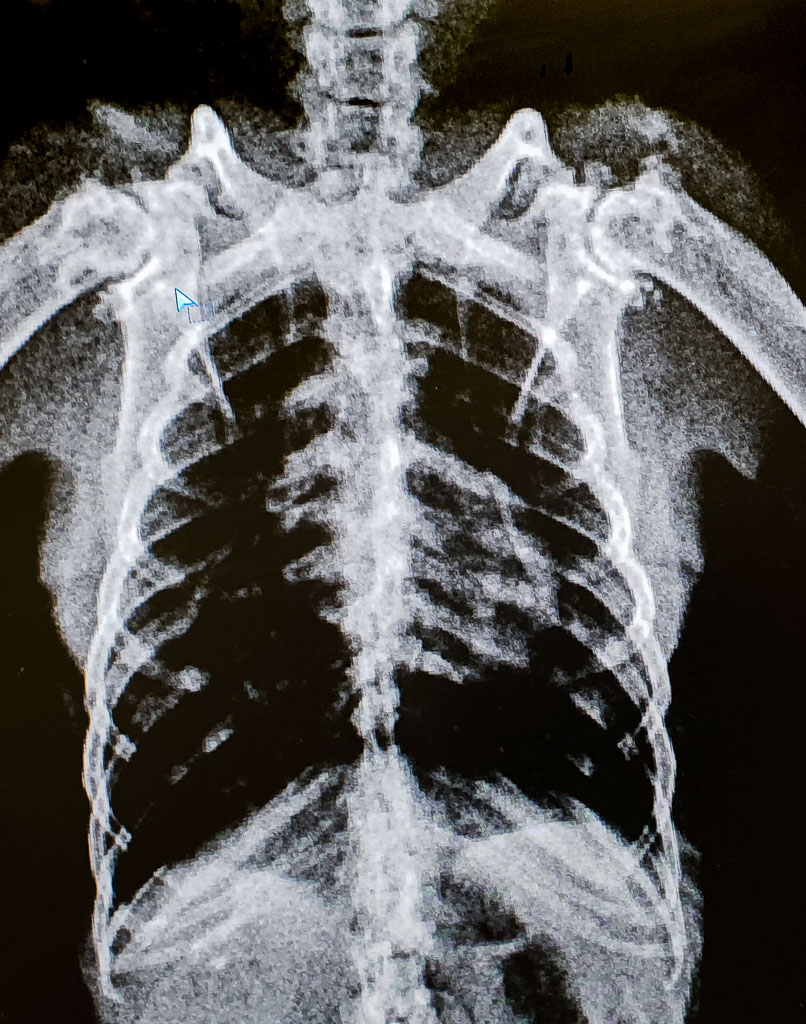

And severe arthritis of the flying joints can result in chronic pain affecting a bat’s ability to fly.

Severe painful arthritis in both shoulders of a rescued old Black Flying-fox.

This often includes a radiology service as well as medication advice and supply. This very much appreciated service provides an exceptional role for the care and rehabilitation of our injured native wildlife.